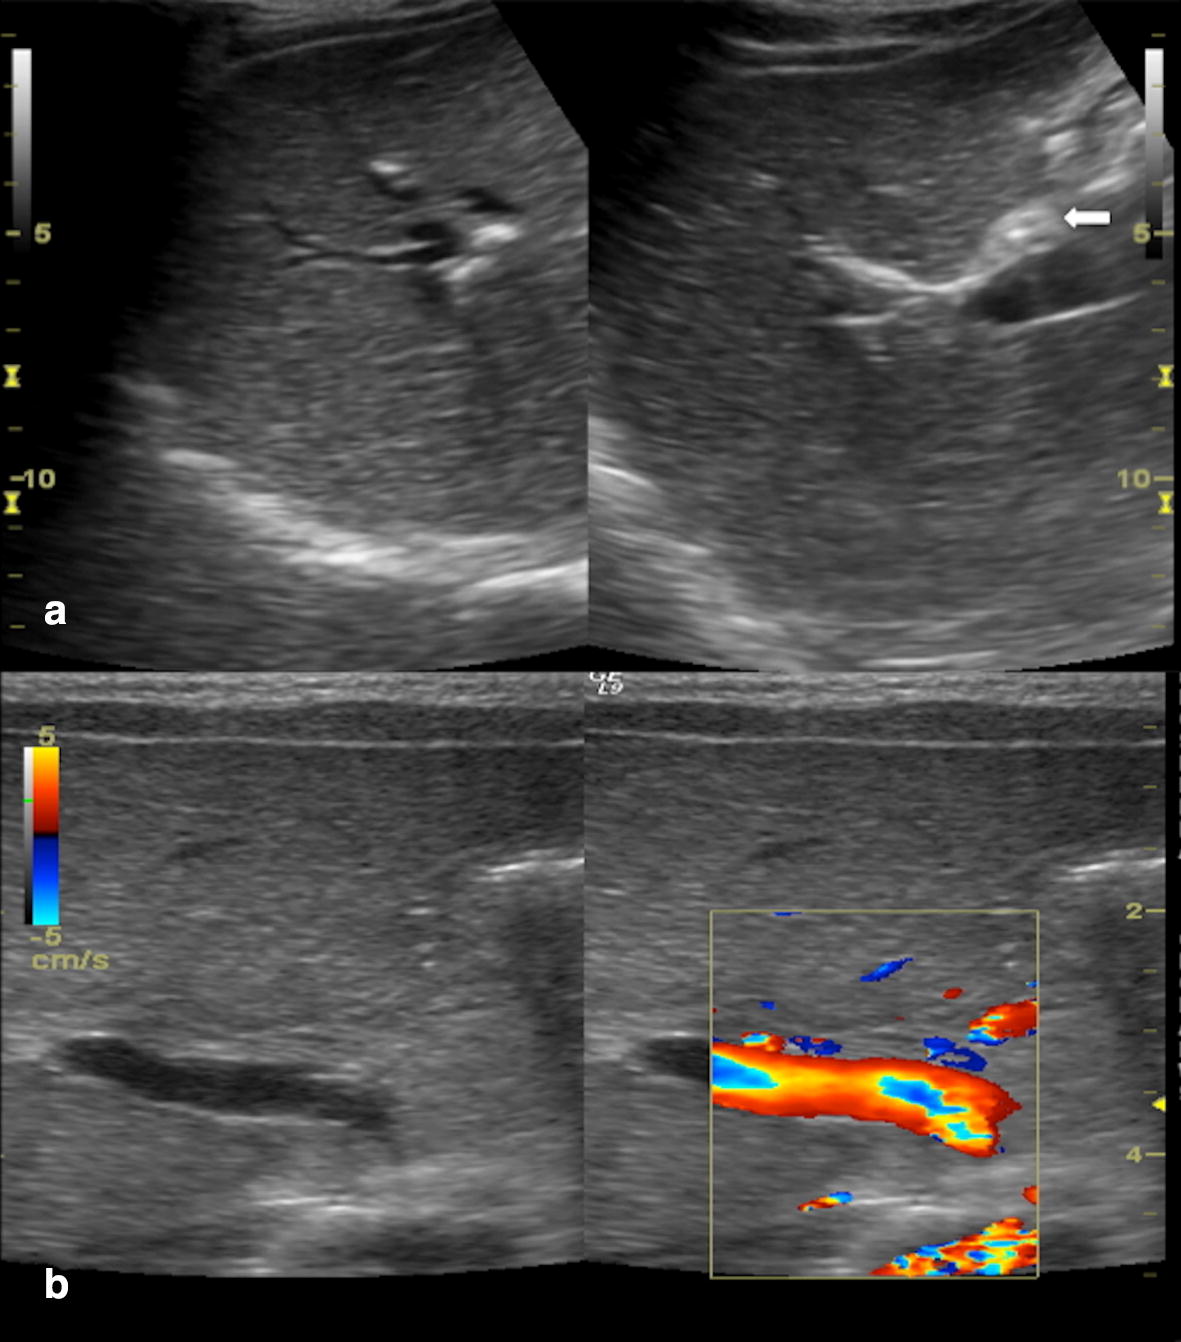

Ultrasound findings in paediatric cholestasis how to image the patient

Ultrasound findings in paediatric cholestasis how to image the patient Cholestasis How To Test  An important initial step in evaluating intrahepatic cholestasis is to document the extent of hepatic dysfunction. A complete medical history and physical exam will be part of a diagnostic assessment for cholestasis. An imaging study , usually ultrasonography, is almost always done if blood test results are abnormal. Serum bilirubin and bile salt levels are elevated in virtually all patients. Cholestasis How To Test.